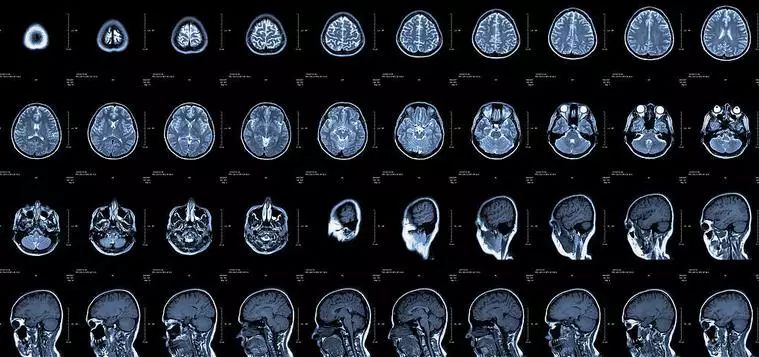

核磁共振机使用较强大的磁场,使人体中所有水分子磁场的磁力线方向一致,这时磁共振机的磁场突然消失,身体中水分子的磁力线方向,突然恢复到原来随意排列的状态。简单说就相当于用手摇一摇,让水分子振动起来,再平静下来,感受一下里面的振动。所以,核磁共振(MRI)也被戏说为是摇摇看的检查。